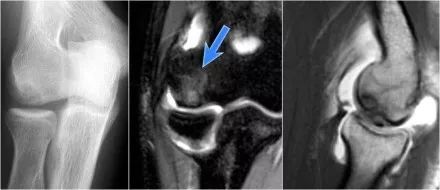

肘关节脱位这是一个患者肘部的侧位片。X光片显示关节积液(红色箭头)和冠状突骨折(黄色箭头)。

下面是MR● 冠状图片:侧副韧带完全剥离(黄色箭头)。桡骨头是半脱位的。由于骨折引起的冠突骨髓水肿(红色箭头)。● 矢状面观:桡骨头稍后有点半脱位(黄色箭头)。大量积液和囊后破裂。● 由于冠状突的撞击(红色箭头)导致的头颅后侧的挫伤。所有这些迹象都是后脱位的结果。

下面是一名23岁的男性,两周前在滑板时摔到在伸出的手上。在体格检查中,肘部的运动范围减小,并且沿侧面方向有压痛。

矢状面:在肘关节后脱位伴有桡骨头前侧(红色箭头)和髁骨后侧挫伤的骨髓水肿的特征。桡骨小头撞击了小头的后部。

桡骨头后面的结构是环形韧带。由于后脱位,它变得不规则和增厚的。